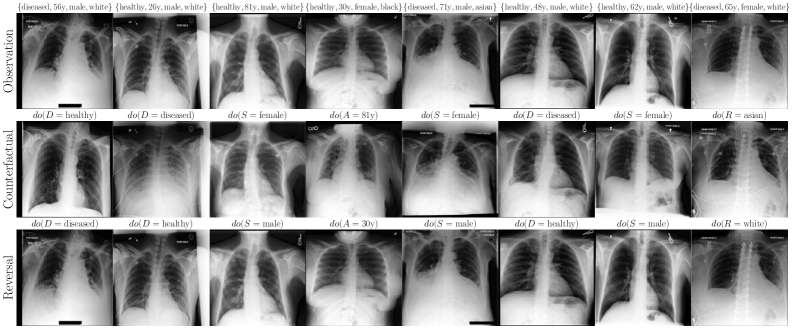

6.2 Case Study: Chest X-ray Imaging Counterfactuals

To extend our study to high-dimensional settings, we conduct experiments on MIMIC-CXR (Johnson et al., 2019), a widely used dataset for counterfactual inference. Our assumed causal graph follows the baselines (Ribeiro et al., 2023; Xia et al., 2024), and includes Sex (), Race (), Age () and Disease () variables, where , and cause the X-ray image . To parameterise our flow models, we use a streamlined version of Dhariwal and Nichol (2021)’s UNet architecture (see Appendix F for details). Table 2 and Figure 4 report our main results. We observe substantial improvements over baselines (Ribeiro et al., 2023; Xia et al., 2024) using our flows, across all three counterfactual soundness axioms, and without requiring any costly counterfactual fine-tuning or classifier(-free) guidance. That said, this alone does not imply causal validity. In Appendix F, we report additional comparisons and ablations. We observe performance trade-offs: for instance, OT-Flow (which assumes Markovianity) outperforms on race interventions but underperforms Flow on disease interventions, suggesting non-Markovian interaction effects or a subpar OT approximation. Notably, our Markovian OT coupling substantially improves over the Naive OT flow baseline.